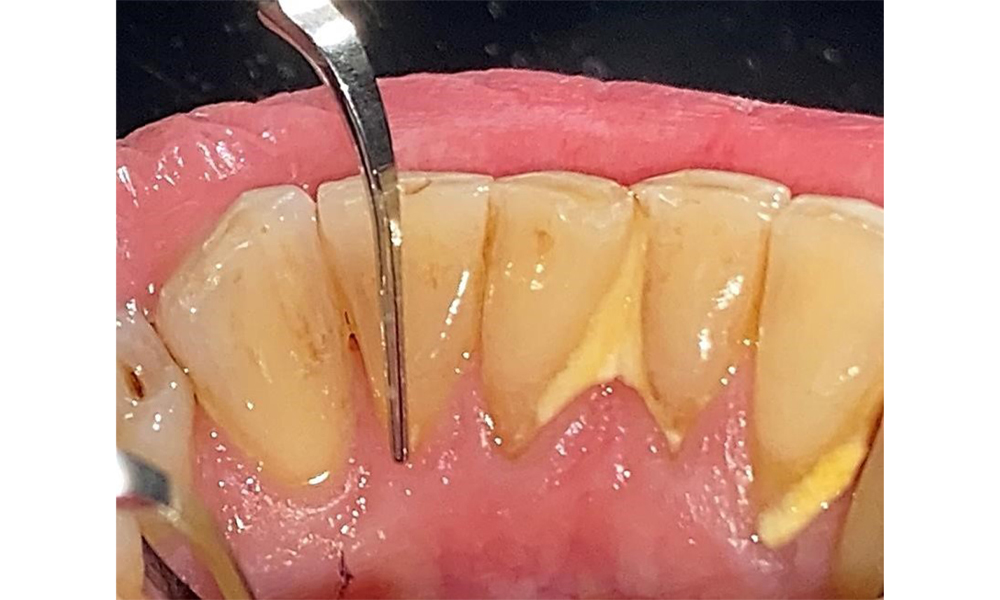

The documentation of periodontal findings, including pocket depth probing and bleeding status, is mandatory during each dental appointment due to the presence of periodontitis (Fig. 8). This will record the individual therapeutic needs and facilitate a rapid response to any progression of the pre-existing periodontitis.

Probing to document the findings in tooth 27 mesiopalatal. © Dr R. Krapf

Fig. 8: Probing to document the findings in tooth 27 mesiopalatal. © Dr R. Krapf

Detailed periodontal findings, including the documentation of pocket depths, bleeding on probing, recessions, furcation involvement and degree of loosening, must be examined annually.